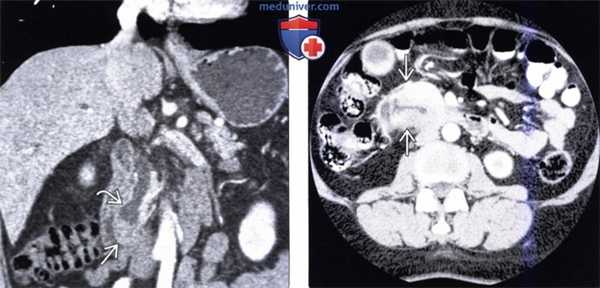

(Слева) На аксиальной КТ с контрастным усилением, выполненной мужчине 49 лет с жалоба -ми на боль в животе и нарушением функции печени, определяется расширение внутрипеченочных желчных протоков.

(Справа) На аксиальной КТ с контрастом определяется также расширение панкреатического протока. Эти изменения позволяют предположить злокачественное новообразование, расположенное в Фатеровой ампуле или возле ее, которое и послужило причиной обструкции.

(Слева) На аксиальной КТ с контрастным усилением у этого же пациента определяется, что головка поджелудочной железы не изменена, в то время как общий желчный проток: в дистальных отделах остается расширенным.

(Справа) На аксиальной КТ с контрастом у этого же пациента определяется большое объемное образование в просвете второй и третьей части двенадцатиперстной кишки, которое обусловливает обструкцию протоков в области относительно низко расположенной Фатеровой ампулы. При эндоскопическом исследовании был подтвержден рак двенадцатиперстной кишки, развившийся в ворсинчатой аденоме.